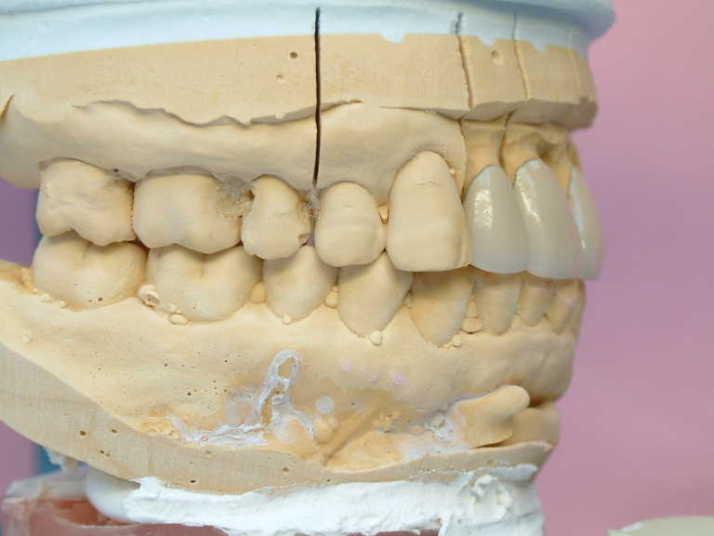

技工士からの回答として

☆下顎前歯の切端を削って頂ければ

2〜2を内側に入れて審美的にも納得して

頂ける補綴物が出来ると思われます。

☆2.2の歯の幅を広げ、1.1の幅を狭くし

全体のバランスを取り作りたいと思います

☆1〜1の間の歯間空隙部分が不自然にならない

よう歯肉模型にて確認しながら製作します |

下顎前歯切端を内側に削って頂いた所 |